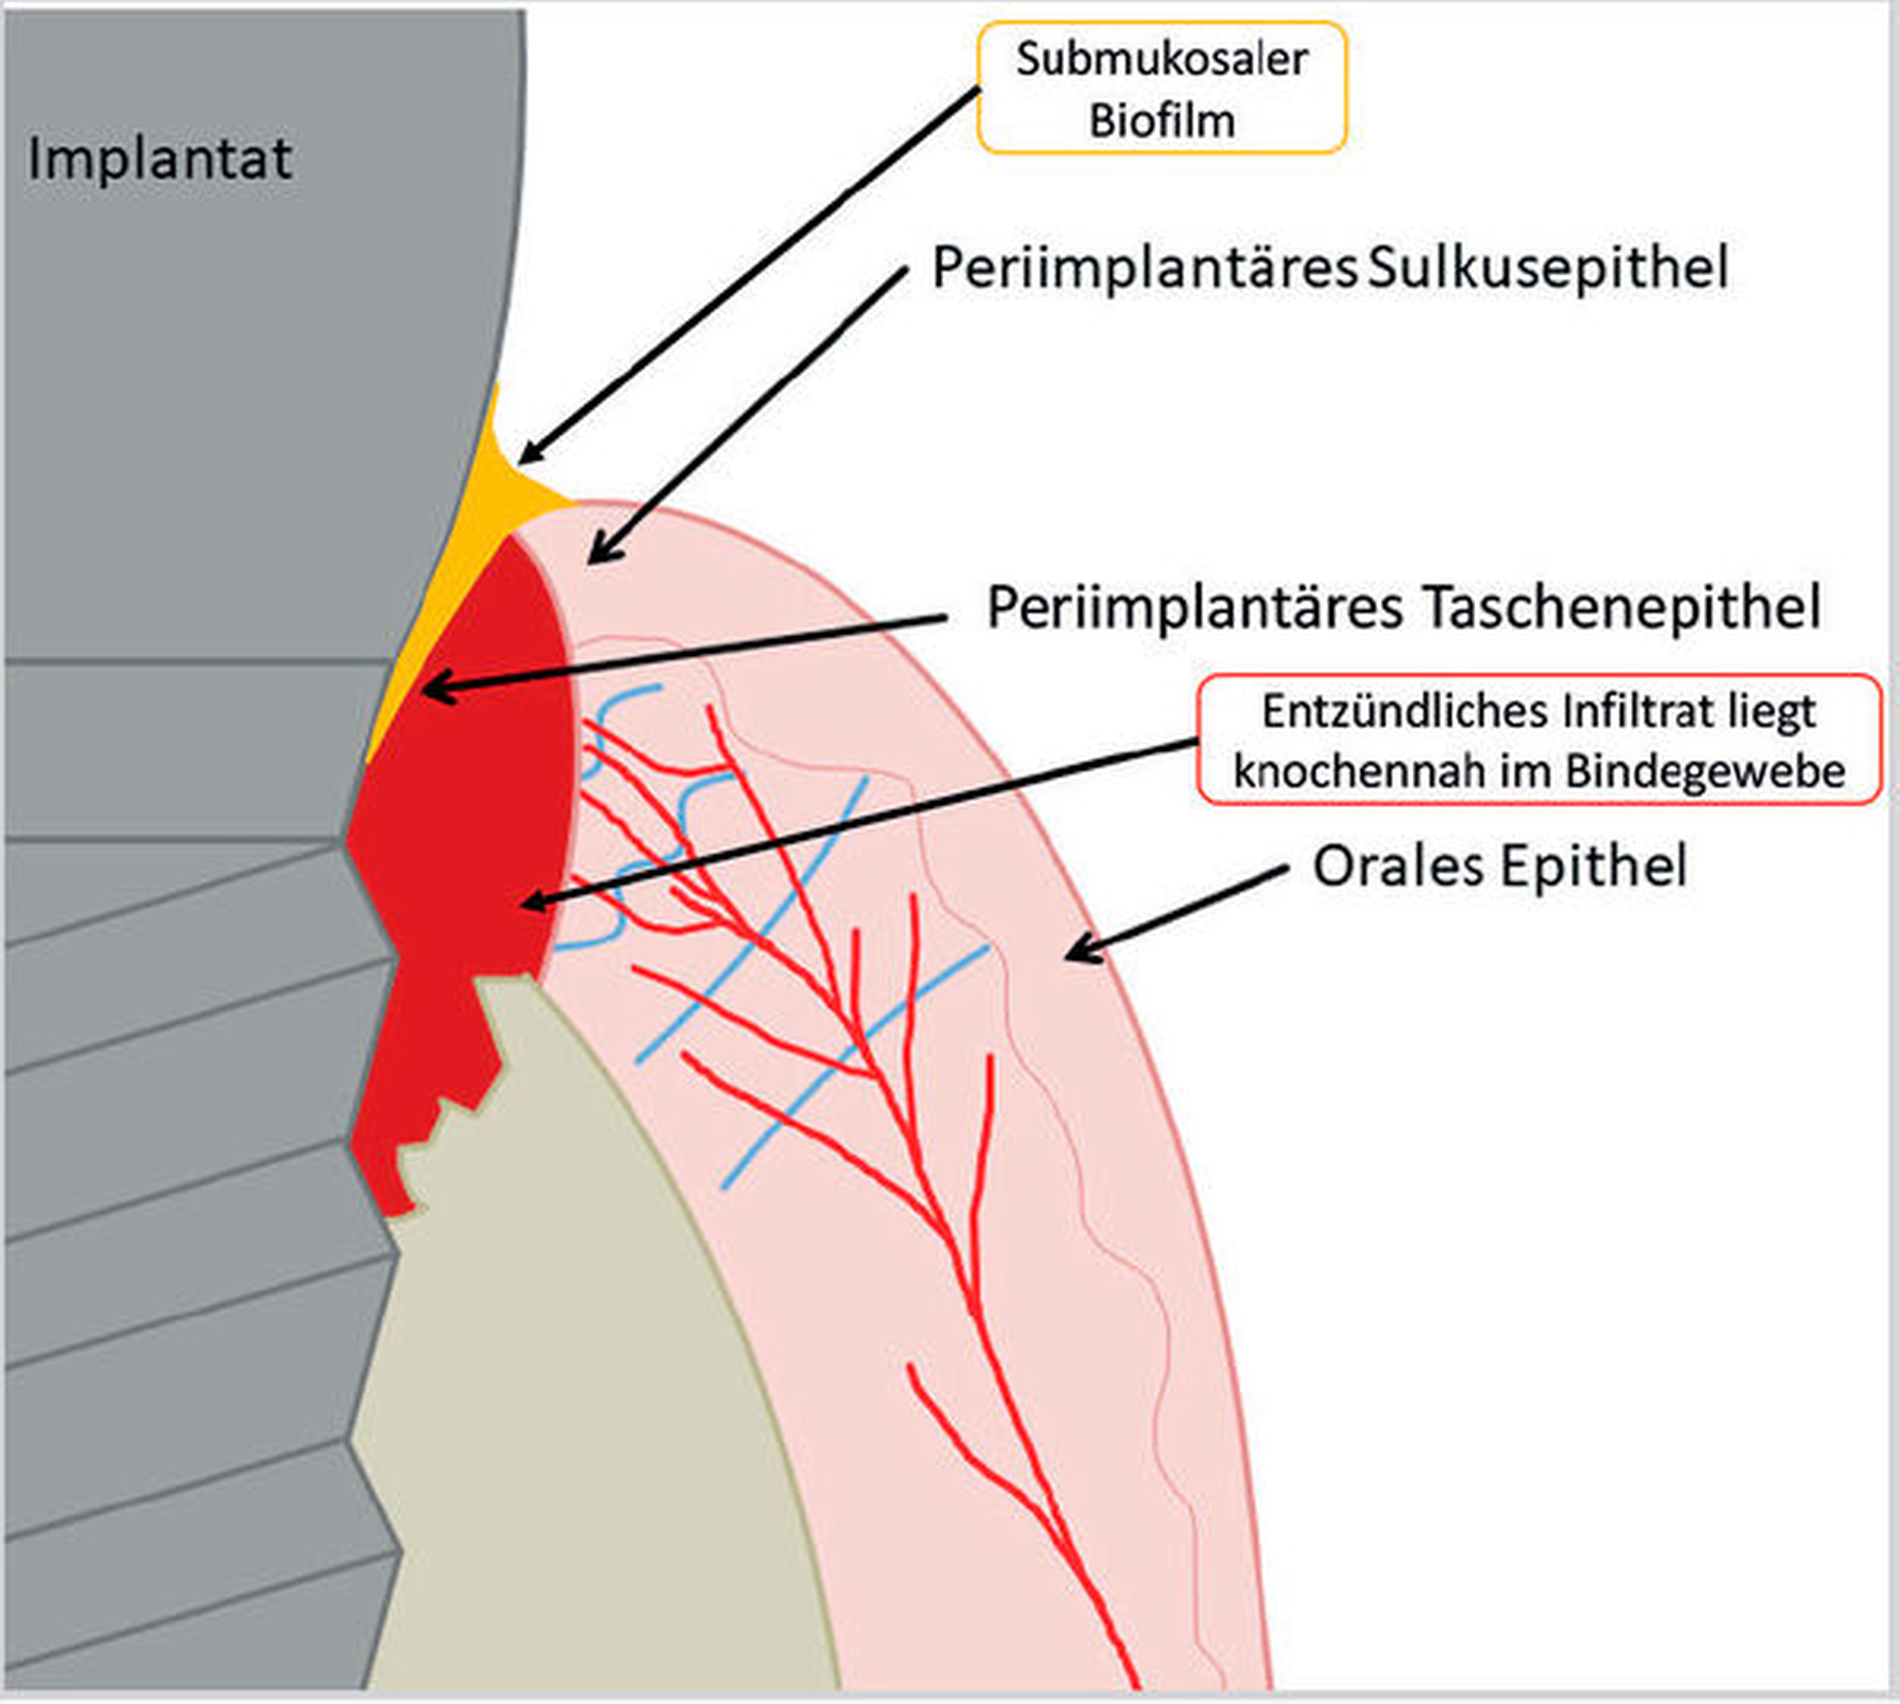

Kommt es jedoch zur Ausbildung einer Inflammation periimplantärer Gewebe ohne Knochenverlust, spricht man von einer periimplantären Mukositis. Wichtigstes Kennzeichen sind dabei die Blutung auf Sondierung und die Begrenzung der Entzündung auf das periimplantäre Saumepithel [Berglundh et al., 2018]. Breitet sich der pathologische Prozess in den Bereich des knöchernen Attachments aus, ist die Destruktion irreversibel und man spricht von einer Periimplantitis (Abbildung 1a). Zusätzlich zu den bereits genannten klinischen Kennzeichen kann man hier auch röntgenologisch den Knochenverlust feststellen, der mit erhöhten Sondierungstiefen und/oder Rezessionen einhergeht [Berglundh, 2019] (Abbildung 1b).

Obwohl sich die Forschung intensiv mit der Ätiologie und den pathologischen Prozessen, die zur Ausbildung einer Periimplantitis führen, auseinandersetzt, sind noch nicht alle Fragen geklärt [Heitz-Mayfield und Lang, 2010]. Fest steht jedoch, dass es sich bei der Periimplantitis um eine plaqueassoziierte chronische inflammatorische Erkrankung handelt. Neben einer Vielzahl von Risikofaktoren, wie eine unzureichende Mundhygiene, fehlende Nachsorge und eine parodontale Vorerkrankung, die die Ausbildung einer Periimplantitis begünstigen, ist die Ursache im Bereich der Plaque und im Gewebe zu vermuten [Renvert und Quirynen, 2015; Schwarz et al., 2018; Sousa et al., 2016; Stacchi et al., 2016].